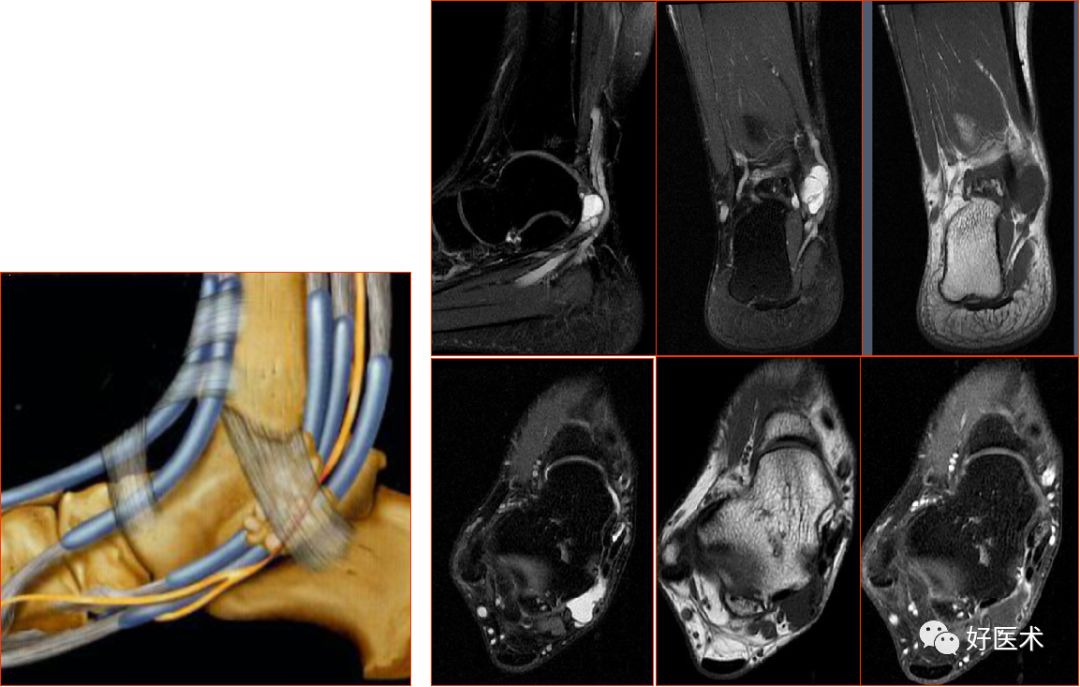

胫骨后肌肌腱撕裂

五、韧带损伤

踝关节的韧带

联合韧带

外侧副韧带

三角韧带

距跟韧带

韧带撕裂的MRI表现

急性韧带撕裂:

慢性韧带撕裂:

胫腓前后韧带:位于胫距关节上方,连接外踝前、后面与胫骨前、后结节,起支持作用

胫腓横韧带:位于胫腓后韧带前下方,后外踝延伸至胫骨关节面后缘,恰好位于内踝的外侧

联合韧带(胫腓前韧带)撕裂

距腓前韧带

距腓前韧带撕裂

距腓后韧带

距腓后韧带部分撕裂

跟腓韧带

跟腓韧带急性完全撕裂

踝关节内侧韧带又称三角韧带,为强劲的三角形纤维束。上方附着于内踝尖及其前后缘;浅层纤维为胫舟部,前行附着于舟骨粗隆,部分与跟舟足底韧带的内侧面融合;中间部为胫跟部,下方附着于载距突;后部为胫距后部,纤维附着于至距骨内侧面和内侧结节。

三角韧带撕裂